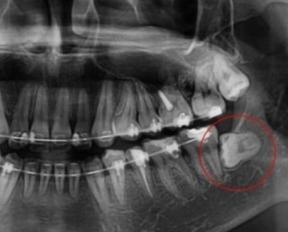

매복 사랑니 발치 후기. 과정, 통증, 팁등...

여러분 매복 사랑니 발치가 얼마나 아픈건줄 아시나여? 진짜 너무 아픕니다 제가 매복 사랑니 발치를 하고 ...